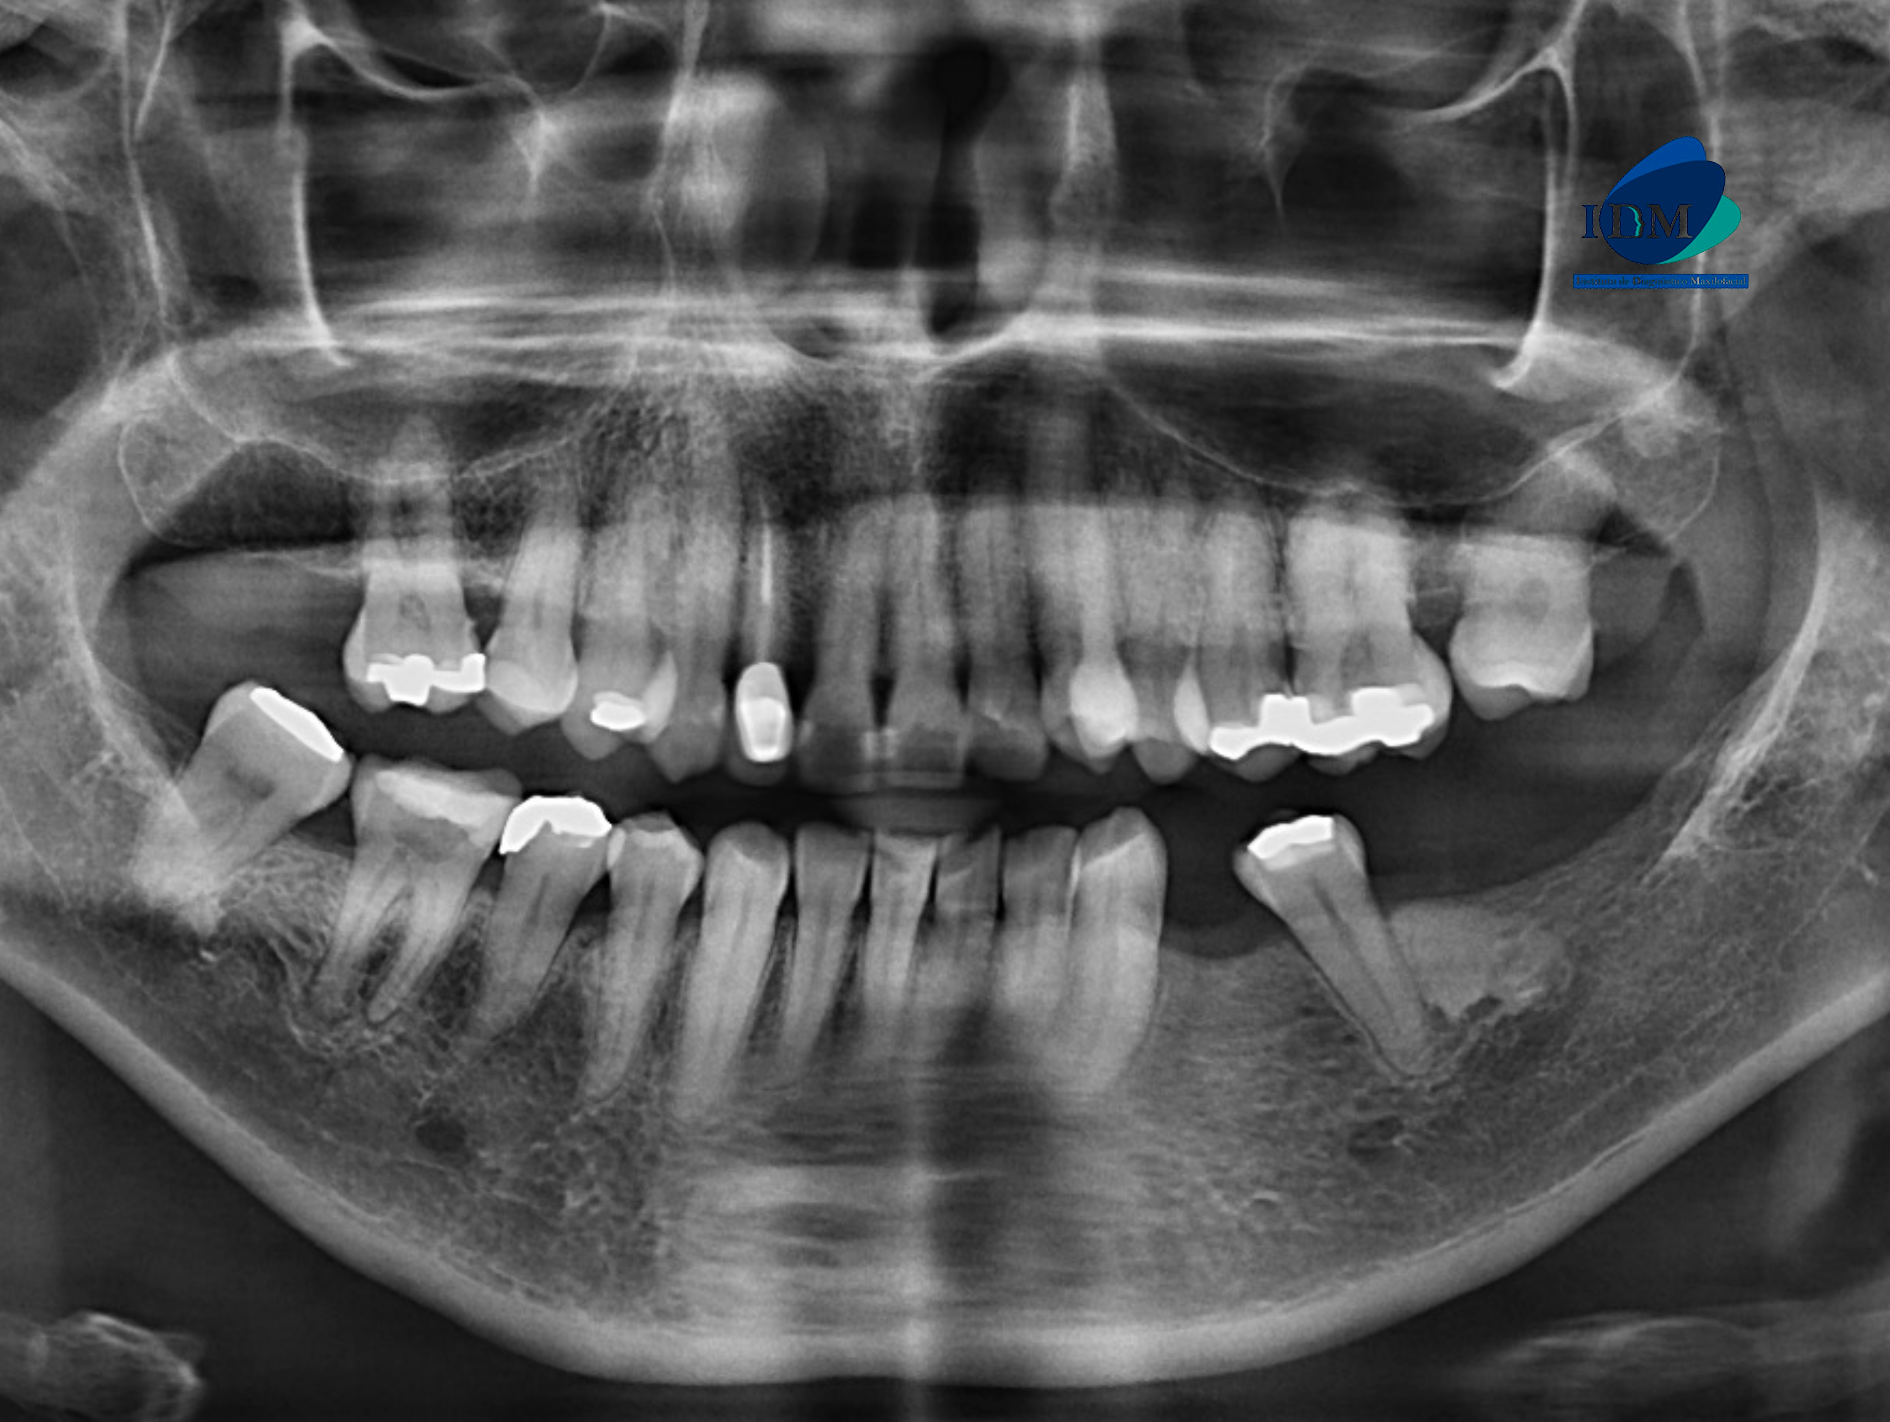

Radiografia Panorámica

A la evaluación de la radiografía panorámica se observa a aplanamiento del contorno condilar bilateral, neumatización de ambos senos maxilares, reabsorción ósea moderada del proceso alveolar, la presencia de una imagen radiopaca de límites definidos y forma irregular en cuerpo mandibular del lado izquierdo compatible con una osteoesclerosis idiopática, múltiples restauraciones coronarias y la pieza 12 que presenta corona protésica, espigo intrarradicular y obturación de conducto.